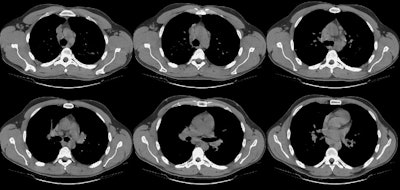

The soft tissue windows on CT scan revealed the presence of mediastinal adenopathy, but no definite hilar adenopathy. Lung windows are below.